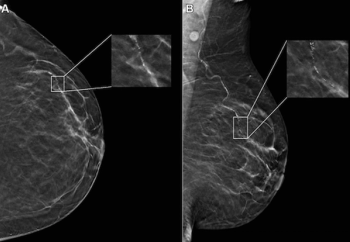

In a study of asymptomatic women at elevated risk for breast cancer, digital breast tomosynthesis (DBT) demonstrated equivalent sensitivity to full-field digital mammography (FFDM) for three out of four reviewing radiologists and detected no additional cancers beyond those detected with FFDM.

Offering comparable sensitivity to radiologists for detecting contralateral breast cancer on mammography images, an emerging adjunctive AI software may also facilitate earlier diagnosis, according to study findings presented at the at the 2024 American Society of Clinical Oncology (ASCO) Annual Meeting.

In a retrospective study involving nearly 119,000 women, researchers found that implementation of AI into mammography screening increased the positive predictive value by 11 percent, increased small cancer detection by 8.3 percent and reduced reading workload by approximately 33 percent.

Researchers also noted that mammography-based AI software was associated with over a threefold higher likelihood of false-positive risk scores in patients 61 to 70 years of age in comparison to women 51 to 60 years of age.